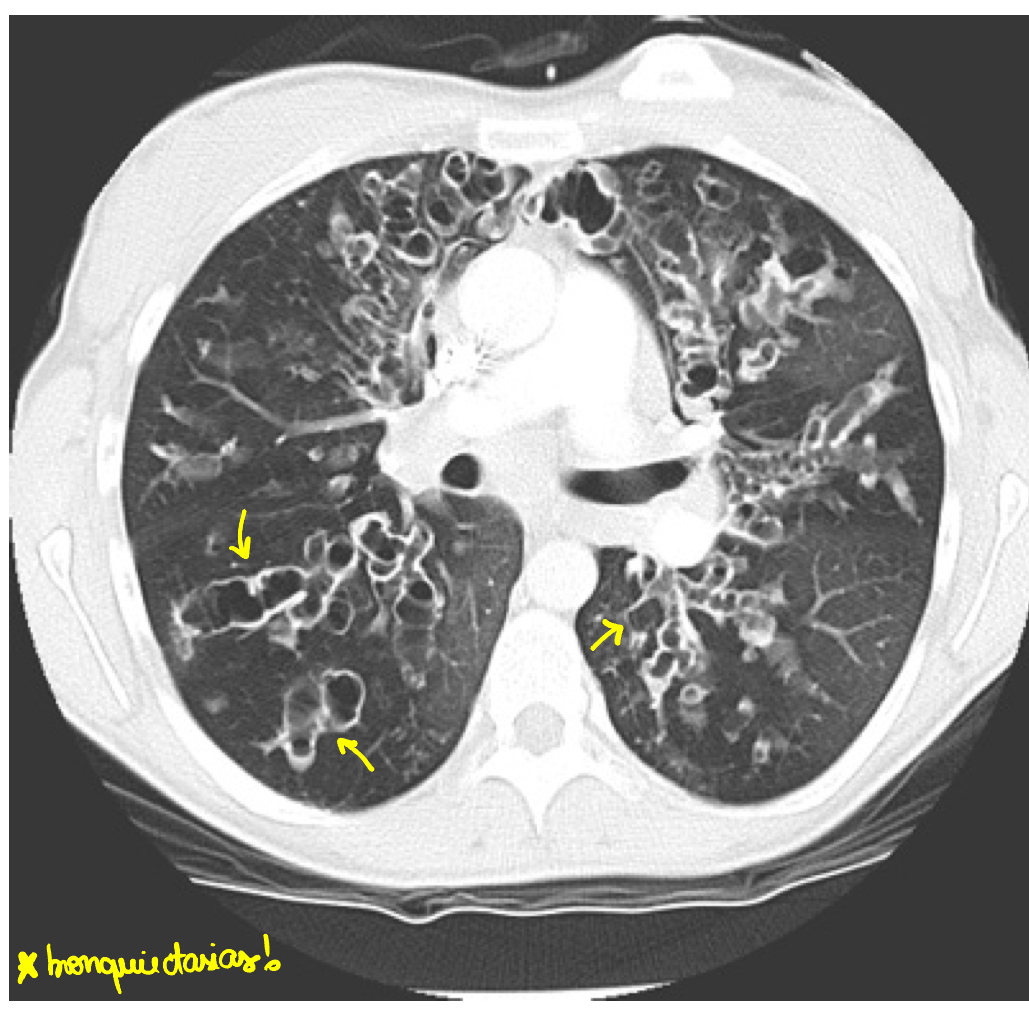

Quais são as manifestações clinicas respiratórias da fibrose cística? O que esperar de QC? Raio X/TC?

• bronquiectasias

RAIO X e TC: bronquiectasias e plugs mucosos

• Raio X/TC: hiperinsuflacao, bronquiectasias, atelectasia, situs inversus

(Predomínio em lobos inferior e lingula)